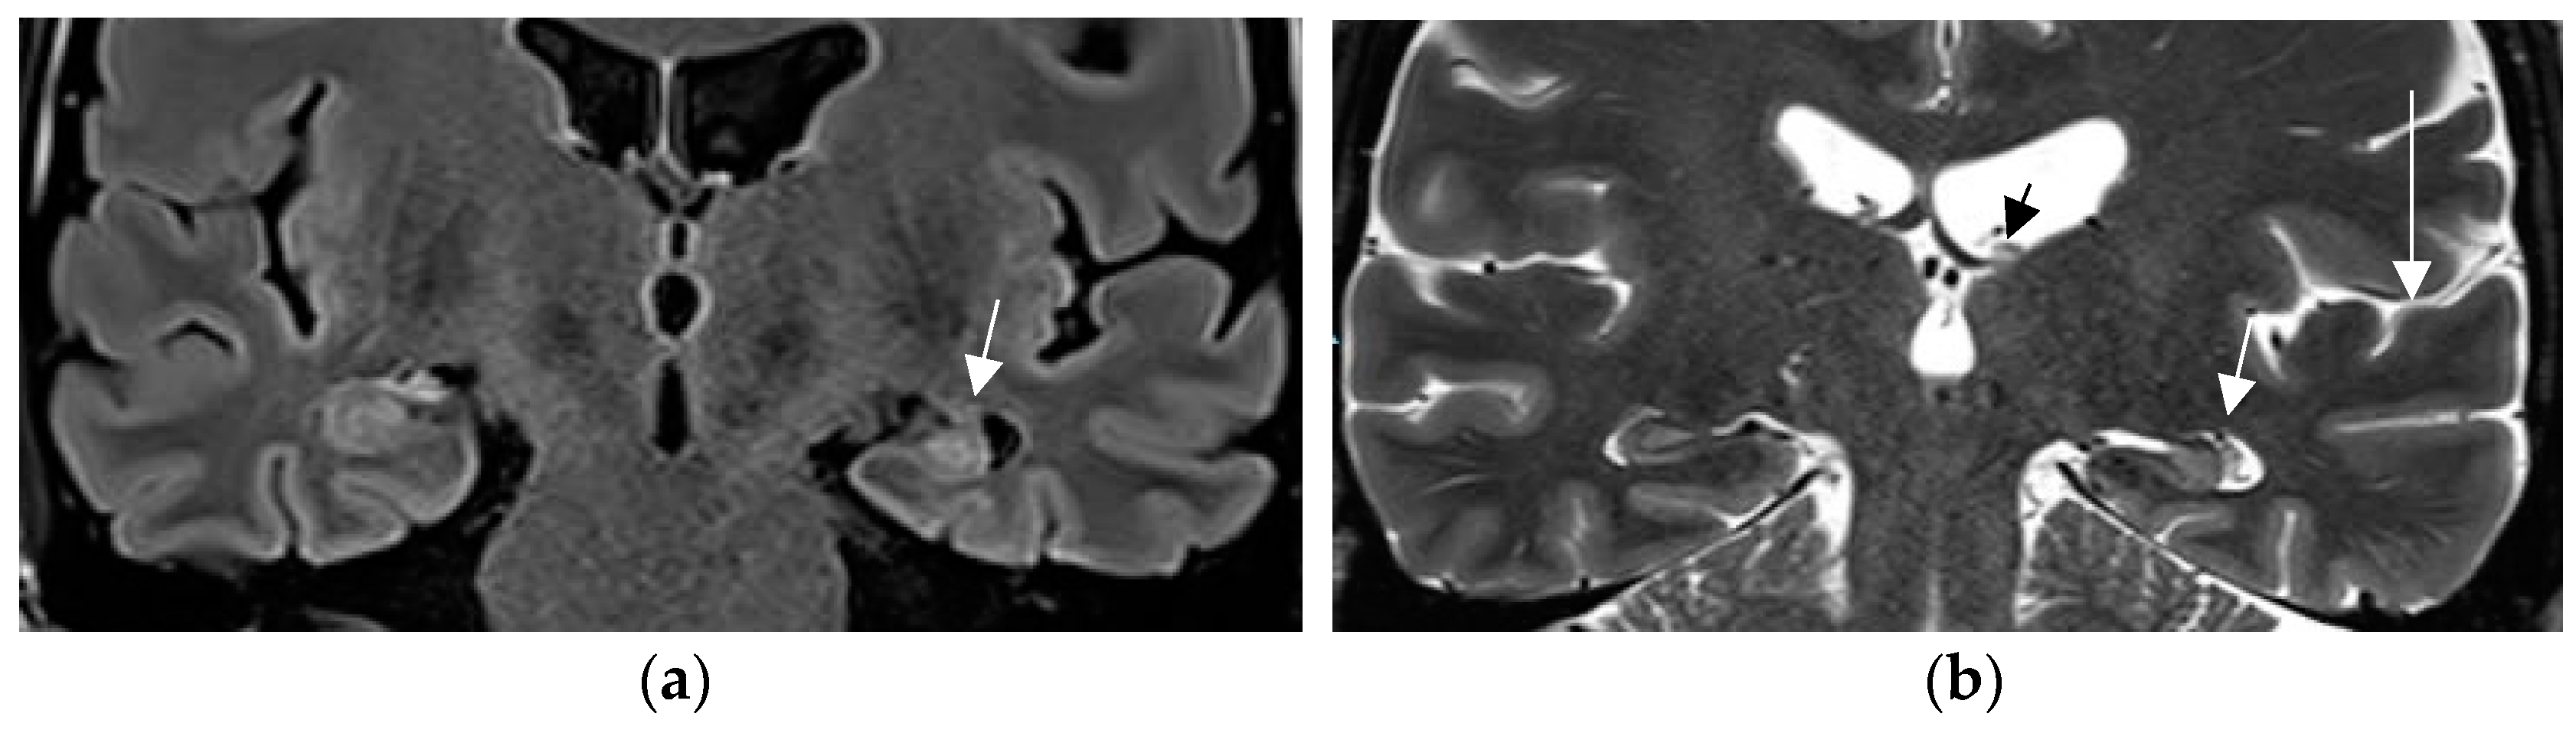

In a prior study [67] and in a recent prospective evaluation of the HARNESS protocol [68] in 123 and 131 patients, the sensitivity of MRI was particularly enhanced through interpretation by experienced readers for the diagnosis of hippocampal sclerosis and focal cortical dysplasia as the previously most frequently missed entities in adults and children, respectively. The combination of a dedicated MR and expert reader assessment increased detection of hippocampal sclerosis from 18 to 45% and of focal lesions from 50 to 91% [67]. Expert readers are more likely to recognize focal hippocampal sclerosis (Figure 2) and detect associated indirect signs such as atrophy of the ipsilateral fornix and mammillary body. Observations like the transmantle sign and subtle changes to adjacent white matter in focal cortical dysplasia and periventricular nodular and subcortical band heterotopia are challenging and less likely to be missed visually by an experienced reader.

Figure 2.

Hippocampal sclerosis depicted on coronal FLAIR (a) and T2 w sequence (white arrows) (b) (1.7 mm each) with volume reduction of the CA1-4 regions of the left hippocampus. FLAIR and T2 signal increases and slight atrophy of the left fornix (short arrow in (b)). Marked volume reduction of left temporal lobe as evidenced by the lower position of the left Silvian fissure (long arrow in (b)) compared to the right side.